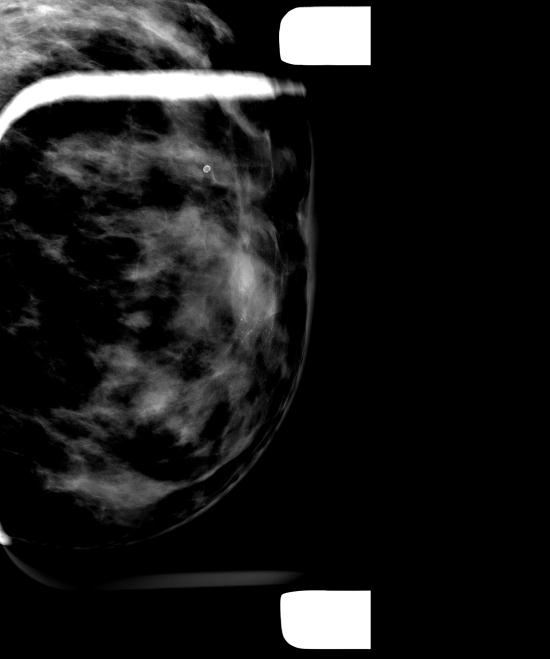

건강검진상 이상소견으로 의뢰된 42세 여성분입니다.

군집된 미세석회화가 좌측유방 하내측에 보이고

유방초음파로 좌측유방 7시방향 유두로부터 2cm 거리에

유관확장과 함께 군집을 이룬 미세석회화가 확인되어 중심핵생검으로

조직검사하여 유관내 상피내암으로 진단되었습니다.